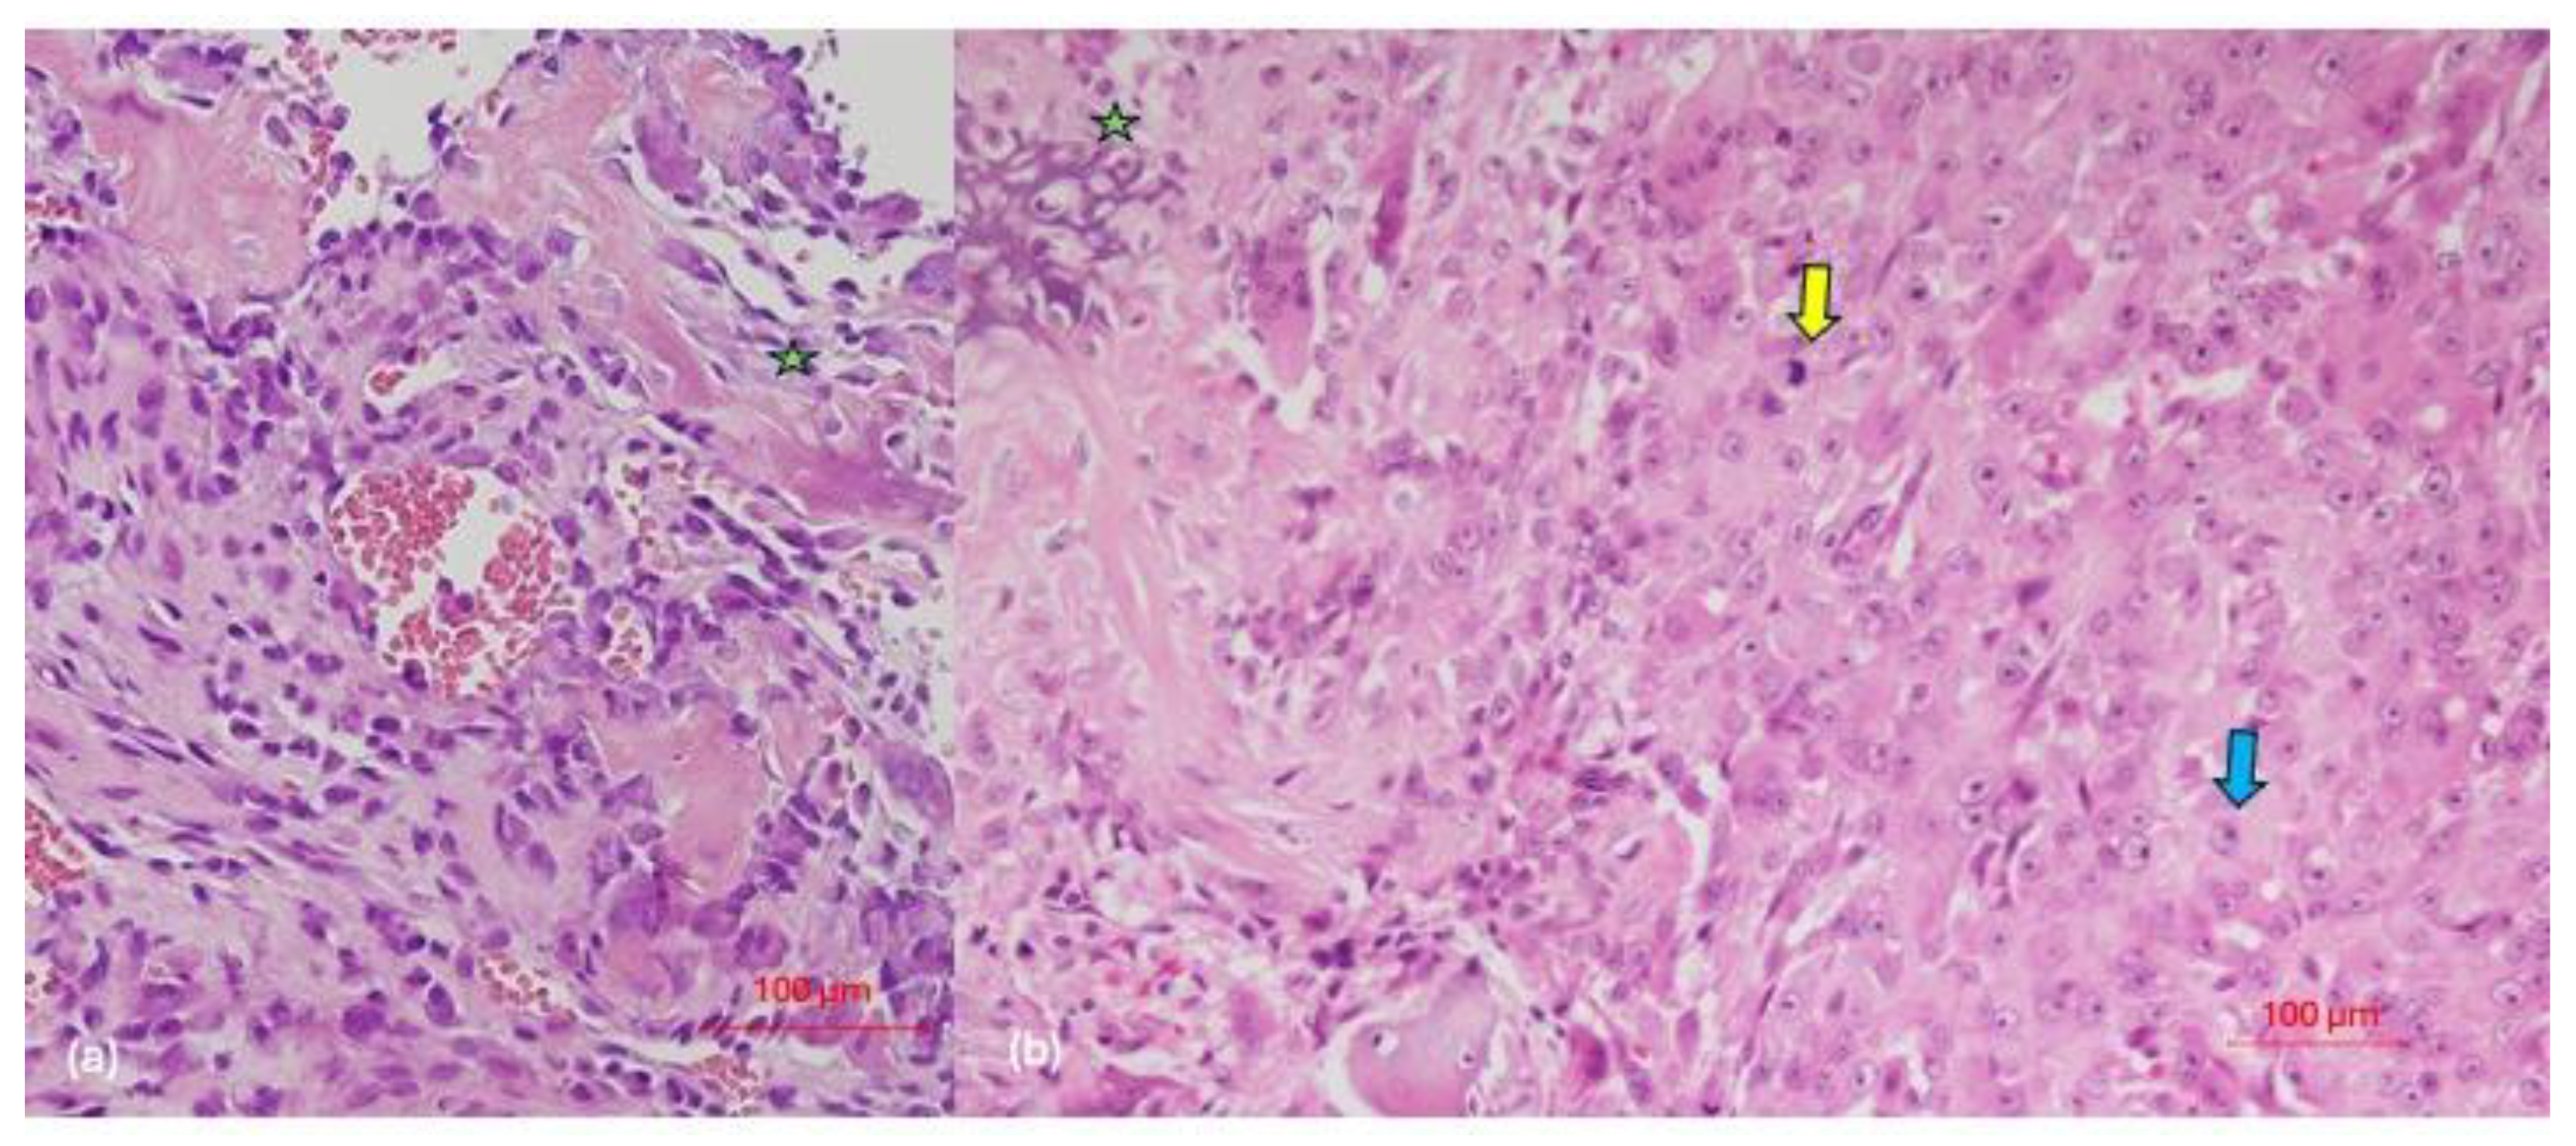

3.2. Pathological Characteristics of Tumor Lesions

| Case | Histological Morphology | Grade | Broder’s Classification | Soft-Tissue Involvement | Lymphovascular Invasion |

|---|---|---|---|---|---|

| 1 | Fibroblastic | High | Grade 3–4 | No | No |

| 2 | Chondroblastic | High | Grade 3 | No Yes (after recurrence) | No Yes (after 3rd recurrence) |

| 3 | Epithelioid | High | Grade 3 | Yes | No |

| 4 | Osteoblastic | High | Grade 4 | No | No |

| 5 | Osteoblastic | High | Grade 3 | Yes | No |

| 6 | Chondroblastic | High | Grade 2–3 | Yes | No |

| 7 | Osteoblastic | High | Grade 4 | No | No |

| 8 | Epithelioid | High | Grade 4 | No | Yes |